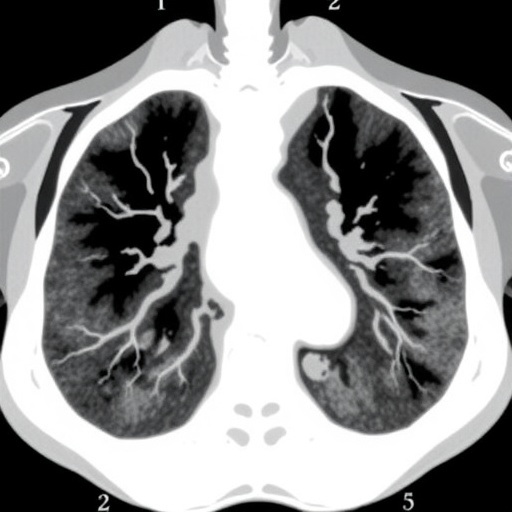

From a technological standpoint, LDCT has been championed as a sensitive modality for early lung cancer detection, delivering detailed tomographic imaging with substantially reduced radiation exposure compared to conventional CT scans. However, the nuanced natural history of lung cancer development, especially in populations with substantial tobacco exposure, requires a more sophisticated interpretation of LDCT’s diagnostic window and its prognostic limitations.

Furthermore, these findings could stimulate technological innovations in imaging and computational analysis. Advanced tomographic modalities, coupled with artificial intelligence-driven image interpretation, could identify subtle, precancerous changes not apparent in conventional LDCT scans, further refining the stratification of high-risk individuals.